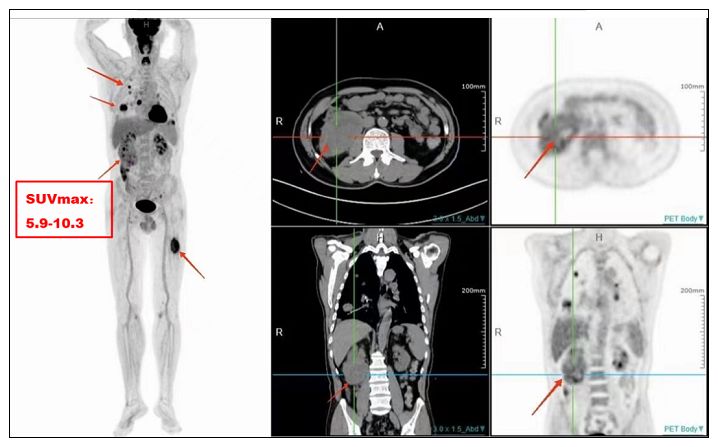

癌细胞比正常细胞更“贪吃”葡萄糖,PET-CT利用这一特性,注射含放射性标记的葡萄糖(FDG)后,通过代谢强度差异,让肿瘤在图像中“发光”。

2.精准分期:一次全身扫描,明确癌症是否转移,避免盲目手术。

3.疗效评估:化疗后肿瘤是否“假死”?PET-CT能分辨活性癌细胞残留。